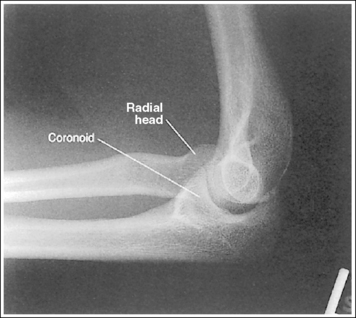

The elbow is in a lateral projection. The distal humerus demonstrates three concentric arcs, which are formed by the trochlear sulcus, capitulum, and medial trochlea. The elbow joint space is open, and the radial head is superimposed over the coronoid process.

• A lateral elbow projection is obtained when the humeral epicondyles are positioned directly on top of each other, placing an imaginary line drawn between them perpendicular to the IR. To obtain this humeral epicondyle positioning, place the humerus parallel with the IR and elevate the distal forearm until the palpable medial and lateral epicondyles are superimposed (Figure 4-78). This positioning aligns the trochlear sulcus, capitulum, and medial trochlea into three concentric (having the same center) arcs (Figure 4-79). The trochlear sulcus is the small center arc. It moves very little when a positional change is made and works like a pivoting point between the capitulum and medial aspect of the trochlea. The largest of the arcs is the medial aspect of the trochlea. It is demonstrated very close to and slightly superimposed on the curve of the trochlear notch. The intermediate-sized arc is the capitulum. When these three arcs are in accurate alignment, the elbow joint is visualized as an open space and the anterior and proximal surfaces of the radial head and coronoid process are aligned.

Figure 4-79 AP (left) and lateral (right) images showing anatomy of the distal humerus. (From Martensen K III: The elbow, In-Service Reviews in Radiologic Technology, 14[11], 1992.)